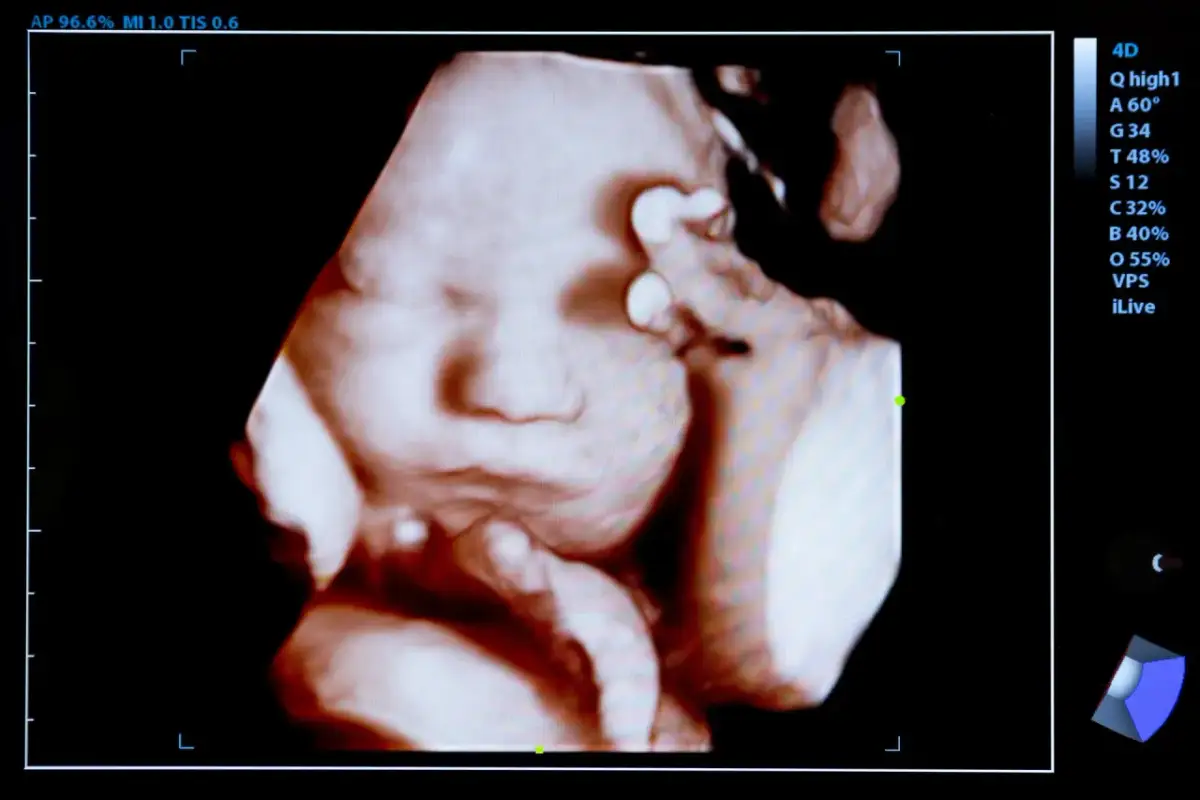

Choć obraz płaczącego dziecka jest nam dobrze znany, to w łonie matki płacz w klasycznym, wokalnym rozumieniu nie jest możliwy. Głównym powodem jest fakt, że pęcherz płodowy jest wypełniony płynem owodniowym. Aby wydać dźwięk, potrzebne jest powietrze, którego płód nie może zaczerpnąć. Mimo to, dzięki nowoczesnej technologii, takiej jak ultrasonografia 4D, naukowcy zaobserwowali u płodów pewne zachowania, które można określić jako "gestalt płaczu". Jest to zespół złożonych reakcji mimicznych, które stają się widoczne szczególnie po 24. do 35. tygodnia ciąży. Obserwuje się wtedy między innymi otwieranie ust, odchylanie głowy, drżenie podbródka oraz specyficzne ruchy oddechowe. Co ciekawe, te reakcje często pojawiają się w odpowiedzi na bodźce zewnętrzne, takie jak hałas czy wibracje. Naukowcy z Uniwersytetu w Durham interpretują te zachowania nie jako wyraz cierpienia, ale jako formę treningu przed narodzinami i ważną oznakę prawidłowego rozwoju mózgu. To fascynujące, jak ciało przygotowuje się do życia poza łonem matki już na tak wczesnym etapie.